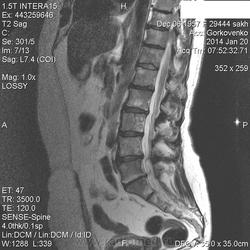

Закон парных случаев-метастатическое поражение позвоночника у женщины зрелого возраста и молодой женщины.У второй-2 года назад удалили ЗНО молочной железы. Жуткое исследование, особенно для оператора, которая училась вместе с пациенткой в медицинском колледже.

В телах позвонков определяются множественные очаги и фокусы разной степени интенсивности понижения МР-сигнала по Т1, Т2 ( первые 2 картинки), неоднородного повышения по Т2 с жироподавлением ( третьи картинки).

Контрастирование  не проводили.